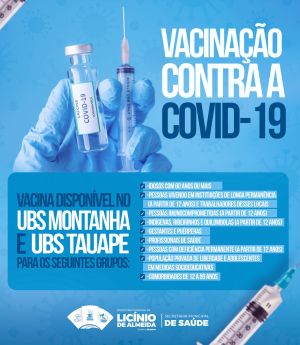

Licínio de Almeida intensifica vacinação contra a Covid-19 nas UBS Montanha e Tauape

Idosos: Pessoas com 60 anos ou mais.

Grupos Vulneráveis: Indígenas, ribeirinhos e quilombolas (a partir de 12 anos).

Saúde e Instituições: Profissionais de saúde, trabalhadores e residentes (a partir de 12 anos) de Instituições de Longa Permanência.

Condições Médicas: Pessoas imunocomprometidas e indivíduos com deficiência permanente (a partir de 12 anos). Além disso, pessoas com comorbidades na faixa etária de 12 a 59 anos.

Gestantes e Puérperas: Mulheres grávidas ou no período pós-parto.

Sistema Prisional: População privada de liberdade e adolescentes em medidas socioeducativas.

Serviço: Os interessados devem comparecer à UBS Montanha ou UBS Tauape portando documento com foto, CPF e a caderneta de vacinação. O horário de funcionamento padrão das unidades de saúde do município é de segunda a sexta-feira, geralmente das 08h às 12h e das 14h às 17h.